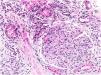

Renal biopsy revealed a diffuse endoproliferative (mesangioproliferative pattern) exudative sclerosing glomerulonephritis with collagen III deposition within mesangium and capillary walls, accompanied with diffuse chronic fibrosing mononuclear tubulo-interstitial nephritis. Immunocomplex glomerulonephritises were excluded (Figs. 1 and 2).

Collagen type III nephropathy (Col3NP) is a rare glomerular disease with characteristic accumulation of abnormal collagen type III in glomerular mesangium and subendothelial space and increase in serum PIIIP levels.1 The etiopathogenesis remains unclear, but ethnic and/or genetic factors may play a role.2 Some authors suggested autosomal recessive inheritance pattern, whereas in our case the occurrence of disease was sporadic.3

Type III collagen is a structural protein of extracellular matrix and is present in tissues showing elastic properties. In kidney it is normally present only in the interstitium and blood vessels, but not in the glomerulus.4 Although the pathogenesis of this disease is still unknown, two explanations have been proposed. One is the mesangial production of abnormal collagen, another is mesangial accumulation of type III collagen derived from other organs.5